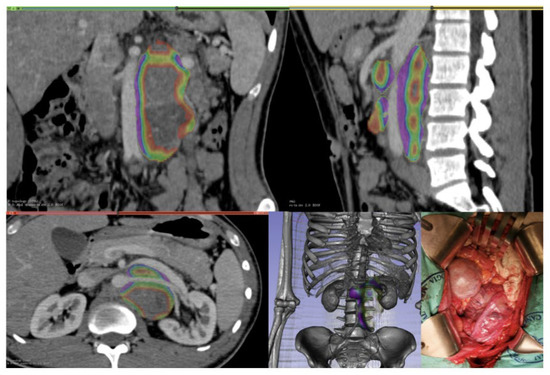

Table 1 summarizes the clinical information of the patients included in this study (n = 60). The median age of all patients was 25.50 (IQR = 17–56). The median size of the residual tumor was 89 cm3. There were no significant differences between the two subgroups. Figure 1, Figure 2, Figure 3 and Figure 4 are examples of prospective cases in which the tumor analyzed pre-operatively with 3D images is totally resected by a young surgeon. No death occurred during the intraoperative and perioperative period in this study.

Figure 2. Para and retro-aortic pure post-puberal teratoma, with CT-rendering and 3D reconstruction; the masses were resected without need for adjunctive procedures.